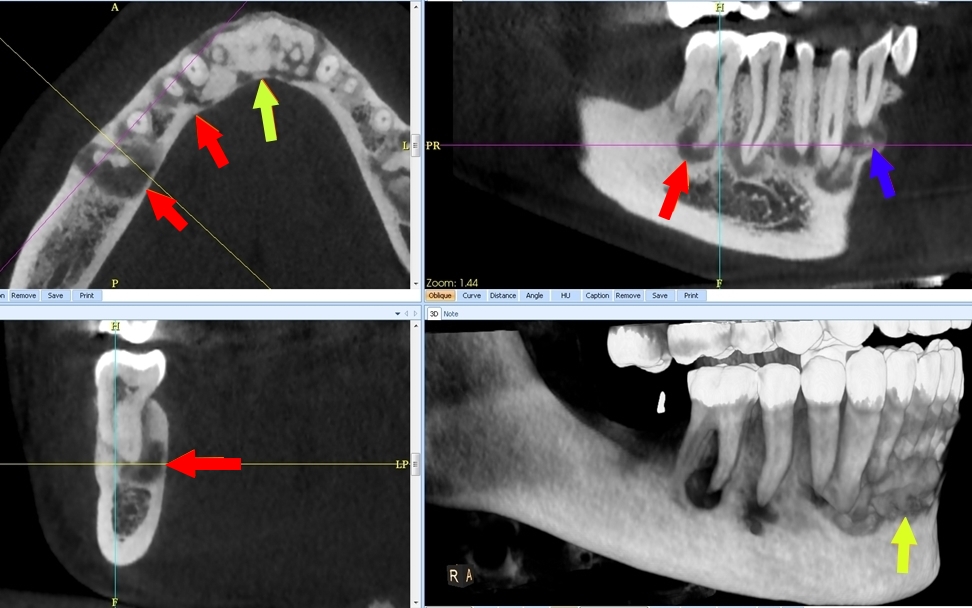

CBCT :

A. Observez sur les reconstructions axiale et panoramique les lésions apicales de :

a.46

b.43

c.et du bloc incisif.

B. Comment les décririez-vous ?

1. Lacunaire (hypodensité homogène) ?

2. En cocarde ou en cible à centre dense (lacune centrée par une zone centrale calcifiée) ?

3. Presque complètement dense, calcifiée (blanche), entourée d’un liseré clair (noir) ?

B. a. 46 : Lacunaire

b. 43 : En cocarde ou en cible à centre dense (lacune centrée par une zone centrale calcifiée).

c : Bloc incisif : Presque complètement dense, calcifiée (blanche), entourée d’un liseré clair (noir).

C. Le diagnostic est : Dysplasie osseuse (anciennement cémento-osseuse) floride.

B. La dysplasie osseuse (ou cémento-osseuse) floride (Fig.4). Elle touche surtout la femme noire d’âge moyen, affectant les deux maxillaires de façon plus ou moins diffuse et symétrique, associant des lésions de grande taille à tous les stades, pouvant s’infecter et se compliquer d’ostéite.